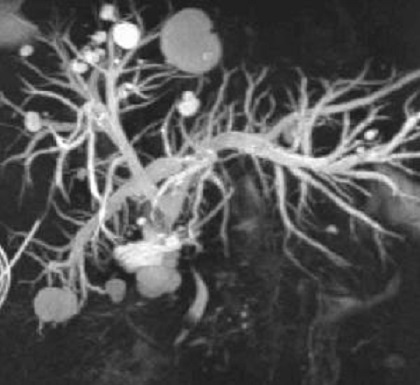

Image radiologique Bili-IRM

d'une kyste choledoque de type Ia recontruit

en 3D . Image de la vesicule biliaire se retrouve

tres nette en position horizontale pres du kyste . |

Dilatation multi kystique

intrahepatique de voie biliaire de type V .(

Maladie de Caroli ). Image radiologique cholangio-IRM

recontruit en 3D de voie biliaire . |